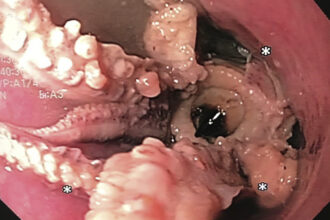

Doctors stunned to find OCTOPUS in patient’s oesophagus

Doctors were stunned to find a half-eaten octopus in a patient’s oesophagus.…